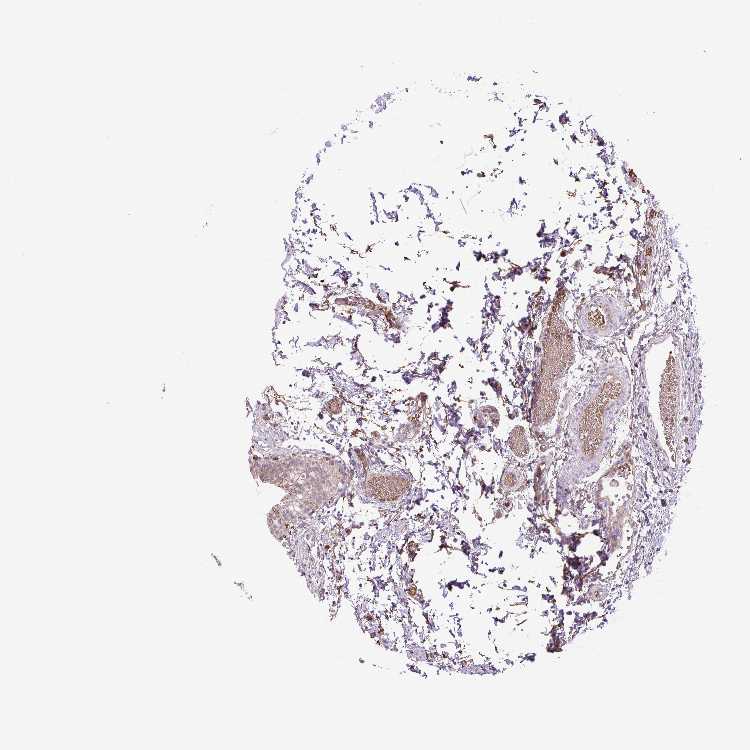

OR13D1